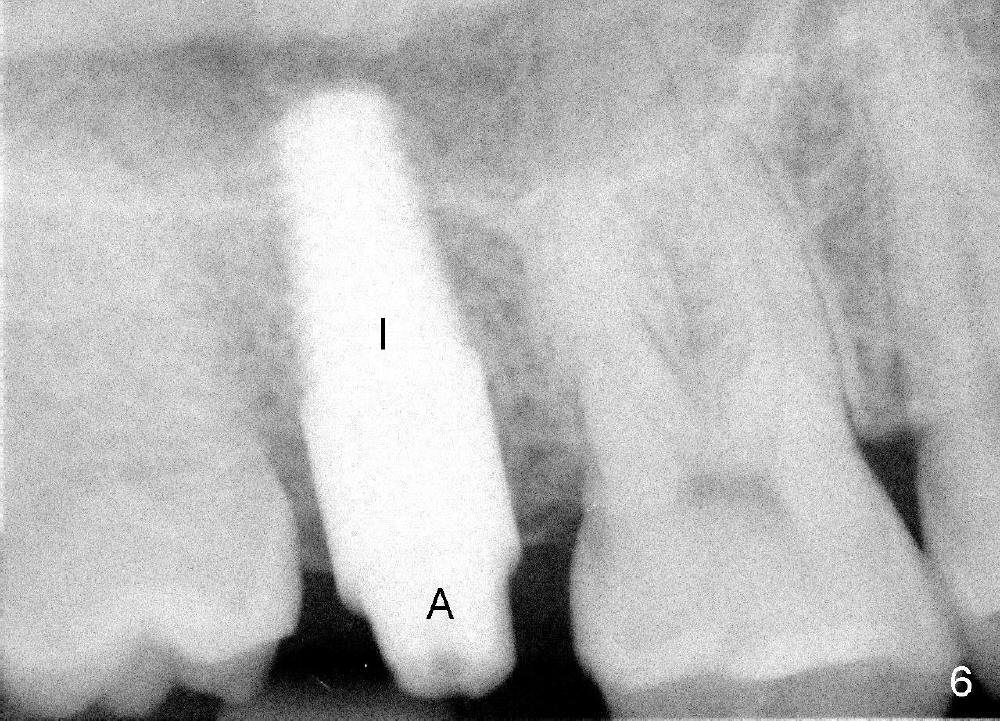

A 42-year-old man is afraid of dentistry. Residual roots of #2 remain untreated for at least 2.5 years (Fig.1). Both the mesiodistal space and the height are limited and unfavorable to restoration (Fig.2,3). Finally he agrees to have treatment, since the tooth #15 is worn so much that it is sensitive to mastication. When the tooth #2 is extracted, the socket is triangular without septum (Fig.4); the bottom of the socket is flat and easy for osteotomy. A 5x17 mm tap has obtained stability once it is placed ~ 14 mm deep (Fig.5). A 5x14 mm implant is placed with insertion torque > 60 Ncm (Fig.6 I), followed by placement of 4x3 mm abutment (A).

To prevent the narrow spaces from getting worse during osteointegration, an immediate provisional is to be fabricated. There is not enough occlusal clearance when the abutment is reduced ~1.5 mm. The abutment is removed; the implant is placed ~ 1 mm deeper with primary stability. Then the occlusal clearance is sufficient; the provisional is made. Mixture of autogenous bone, allograft and Osteogen is placed in the remaining buccal and lingual sockets (Fig.7 *). The provisional is temporarily cemented (Fig.8 P), which keeps the bone graft in place.